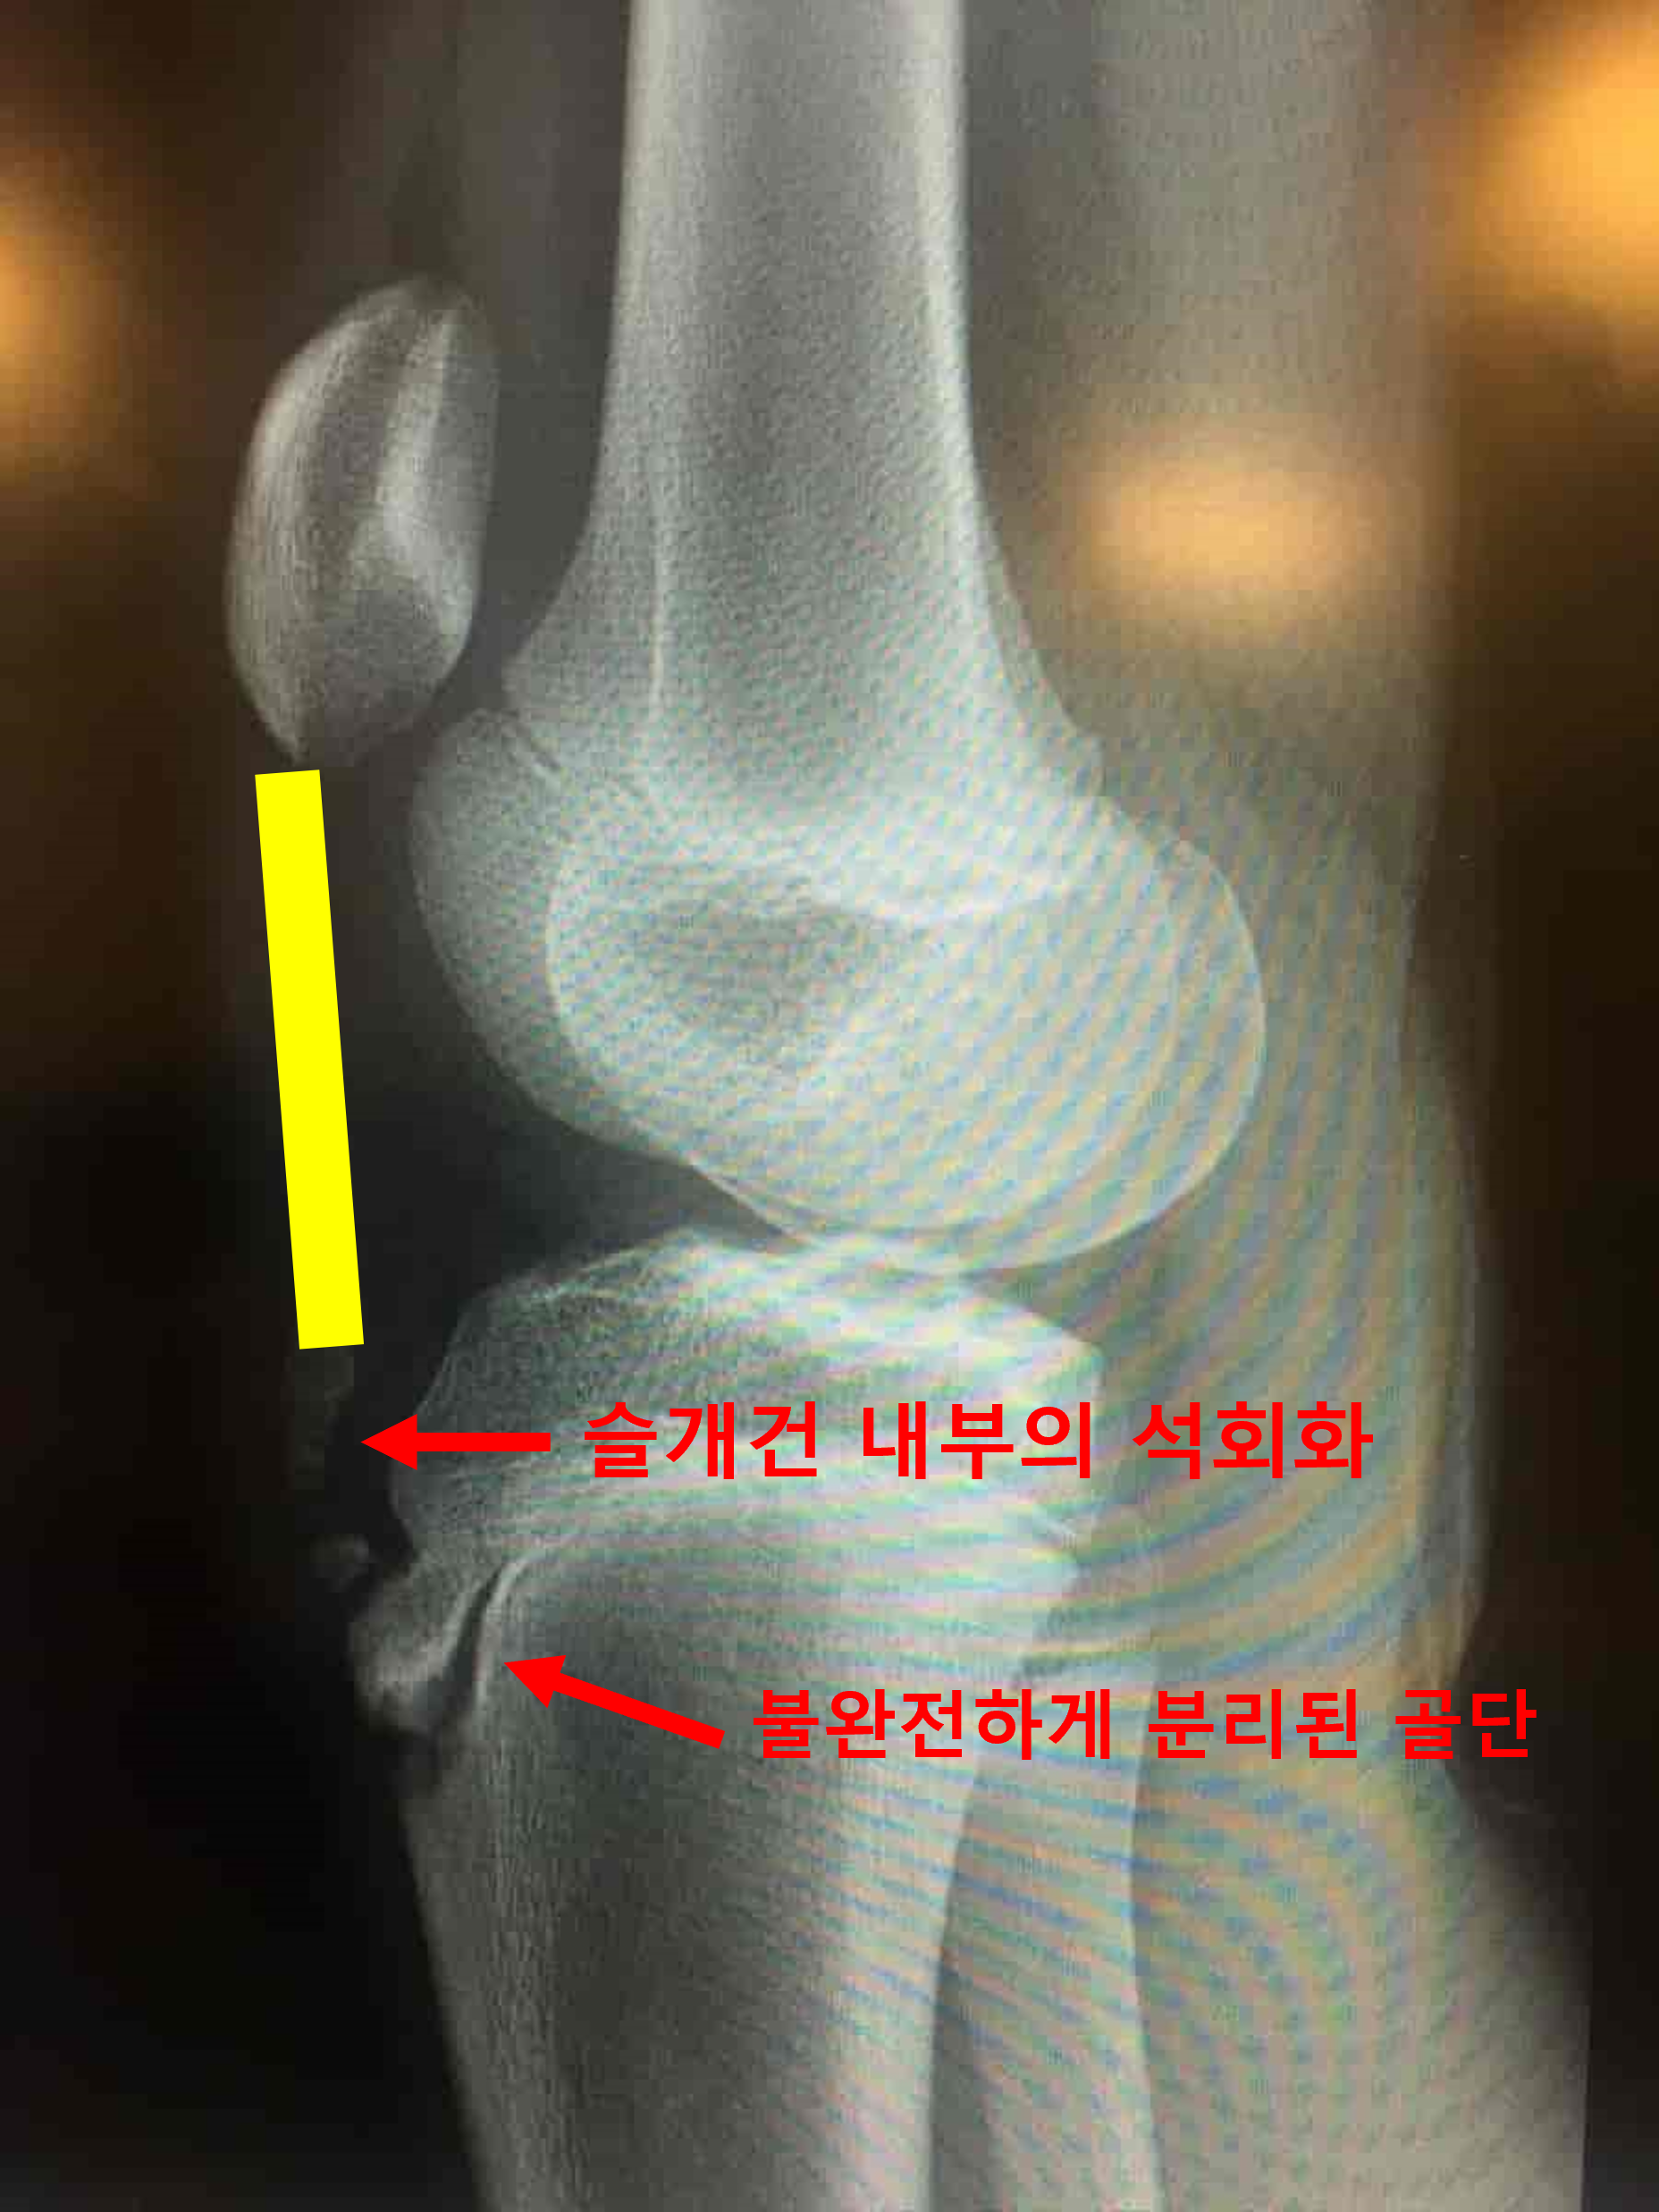

오스굿씨 병의 초기 환자에서는 분리된 골편이 불규칙하게 일부는 붙어있고, 일부는 떨어져나와 보이는 등 균일하지 않은 경계면을 보이게 됩니다. 병변이 진행된 말기에서는 떨어져나온 골편이 명확하게 분리된 것이 보이게되고, 심한 경우 골편이 인대에 견인되어 상방으로 이동해 보이는 경우도 있습니다. 간혹 슬개건 내부에 석회가 낀 것이 보이기도 합니다. (아래 사진 참조,) 이럴 경우에는 외상에 의한 견열 골절 (Avulsion fracture)과 감별이 필요합니다.

내부의 석회가 같이 보이는 경우.